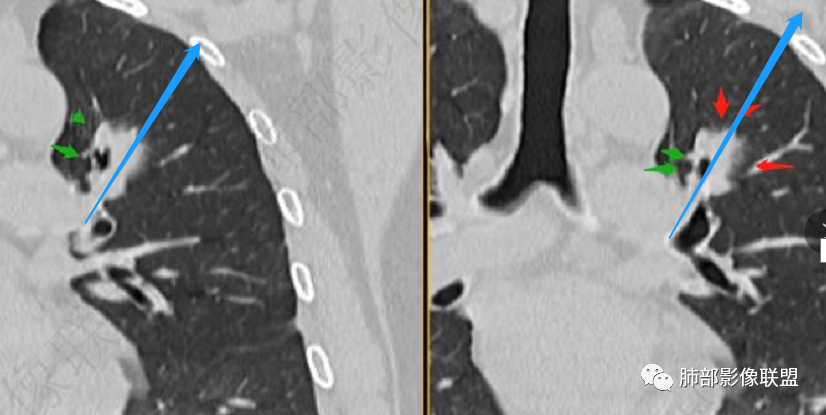

病灶朝前、外侧进展

病灶包括两部分

1、实性2、周围GGO

2、病灶以实性密度为主,前、外侧蔓延,GGO部分边界清楚,部分欠清

支气管未见受明显侵犯,未见阻塞,壁增厚,狭窄或扩张。

1、连续3年观察,病灶逐步增大,符合惰性恶性肿瘤。2、支气管壁增厚,腔内内壁无变化——病灶长轴沿支气管周围蔓延;朝外走,内侧没有,提示病灶间质为主,与支气管无关。

3、GGO长期存在,朝外蔓延,支持恶性特点。

支持淋巴瘤的关键点:1、间质为主;2、与支气管无关;3、边缘GGO的长期存在支持恶性

因为与支气管无关不支持腺癌,还是要警惕淋巴瘤。